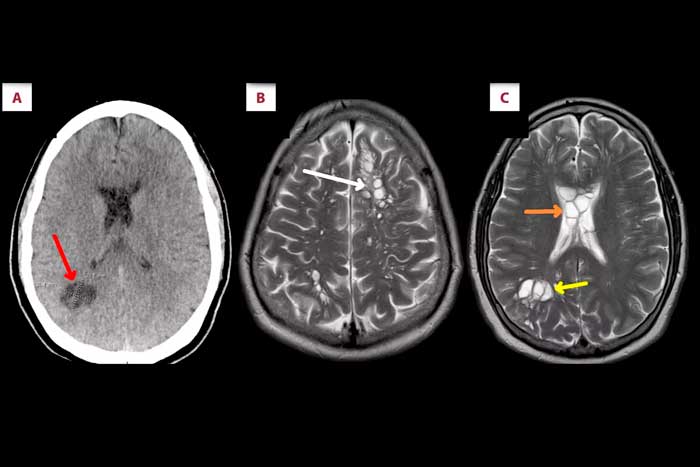

En un procedimiento de rutina, el médico tratante le hizo una tomografía y fue ahí donde hicieron un descubrimiento que al principio los hizo dudar de lo que tenía este pobre hombre y es que parecía que tenía «quistes neurogliales congénitos», que son lesiones quísticas extremadamente raras, su origen es neuroectodérmico y de naturaleza benigna, la cosa es que son poco frecuentes. Pero en una inspección más a detalle, se encontraron con algo mucho más común.

Una vez que analizaron todo con otras pruebas confirmaron que estos «quistes» no lo eran, eran larvas de tenias que habían incubado varios huevos dentro de su cerebro, lo cual estaba afectando su salud, de hecho los quistes larvarios pueden infectar varias partes del cuerpo provocando dolores de cabeza, migrañas, daño neuronal y hasta convulsiones.

Foto: Cortesía People